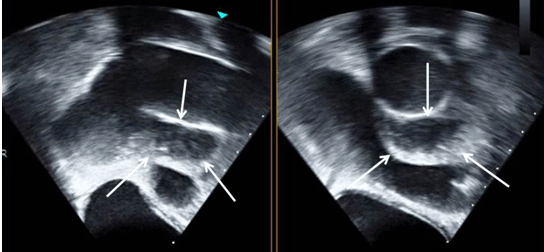

CT Appearance Of Thoracic Aortic Graft Complications

CT of Aortic Graft Complications AJR:188, May 2007 1275 after surgery, and all were asymptomatic. All patients underwent echocardiography, and none of the collections was detected with that ... Document Viewer